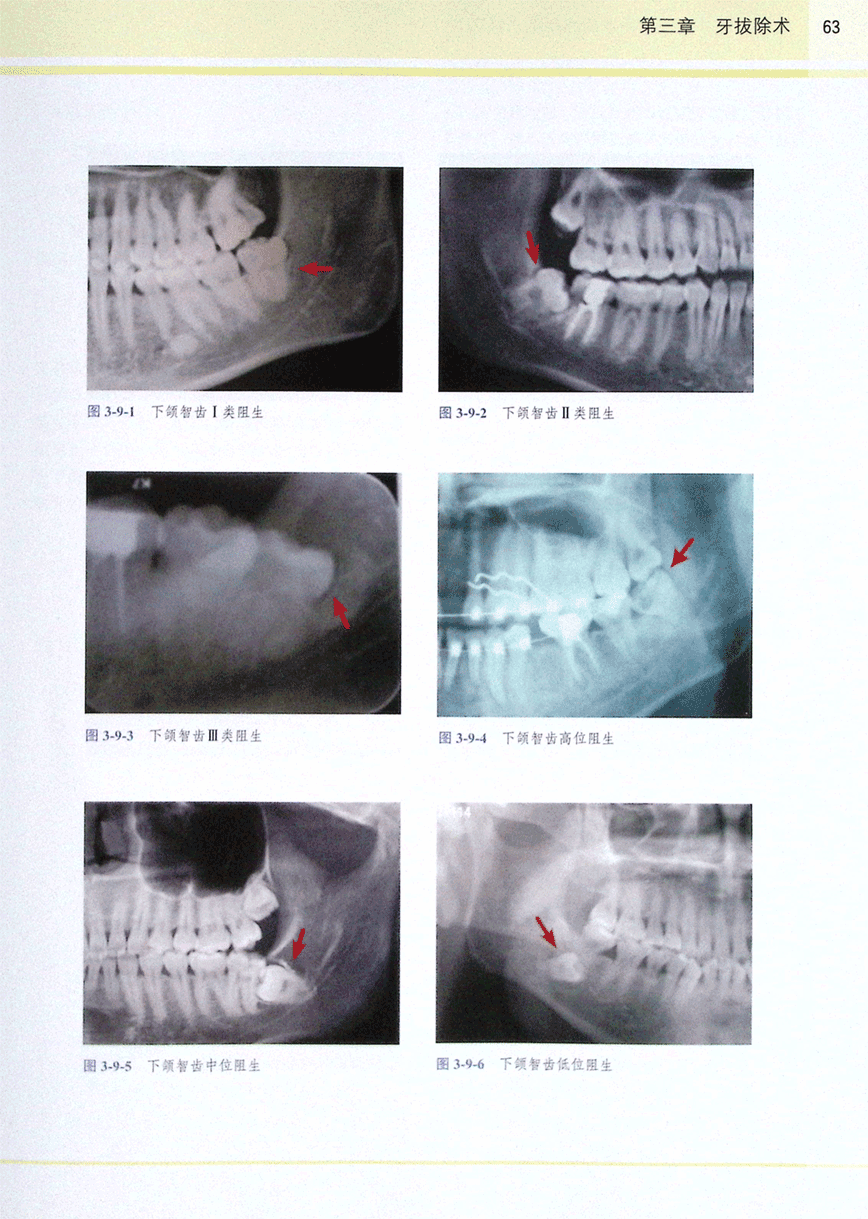

第九节 下颌阻生智齿拔除术(1)